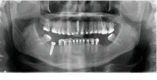

Dental implant surgery is a common procedure in oral and maxillofacial surgery practices. Extensive training, skill, and experience allow this procedure to be performed with an atraumatic approach, but like any surgical technique, it is subject to accidents and complications. This is an unusual clinical case of an accidental displacement of an implant into the submandibular space that progressed to Ludwig's angina, and it has not yet been described in the literature. This case report describes a clinical case of dental implant displaced into the submandibular space after healing cap removal. After seven days, it progressed to Ludwig's angina. The removal was performed through extraoral access in the submandibular area by using hemostatic forceps and radioscopic technique. After implant removal, the clinical case showed a satisfactory repair emphasizing the importance of a meticulous clinical planning to achieve an appropriate treatment plan, which is essential for a favorable prognosis. Therefore, prevention and management of displaced objects requires proper planning and surgical technique.